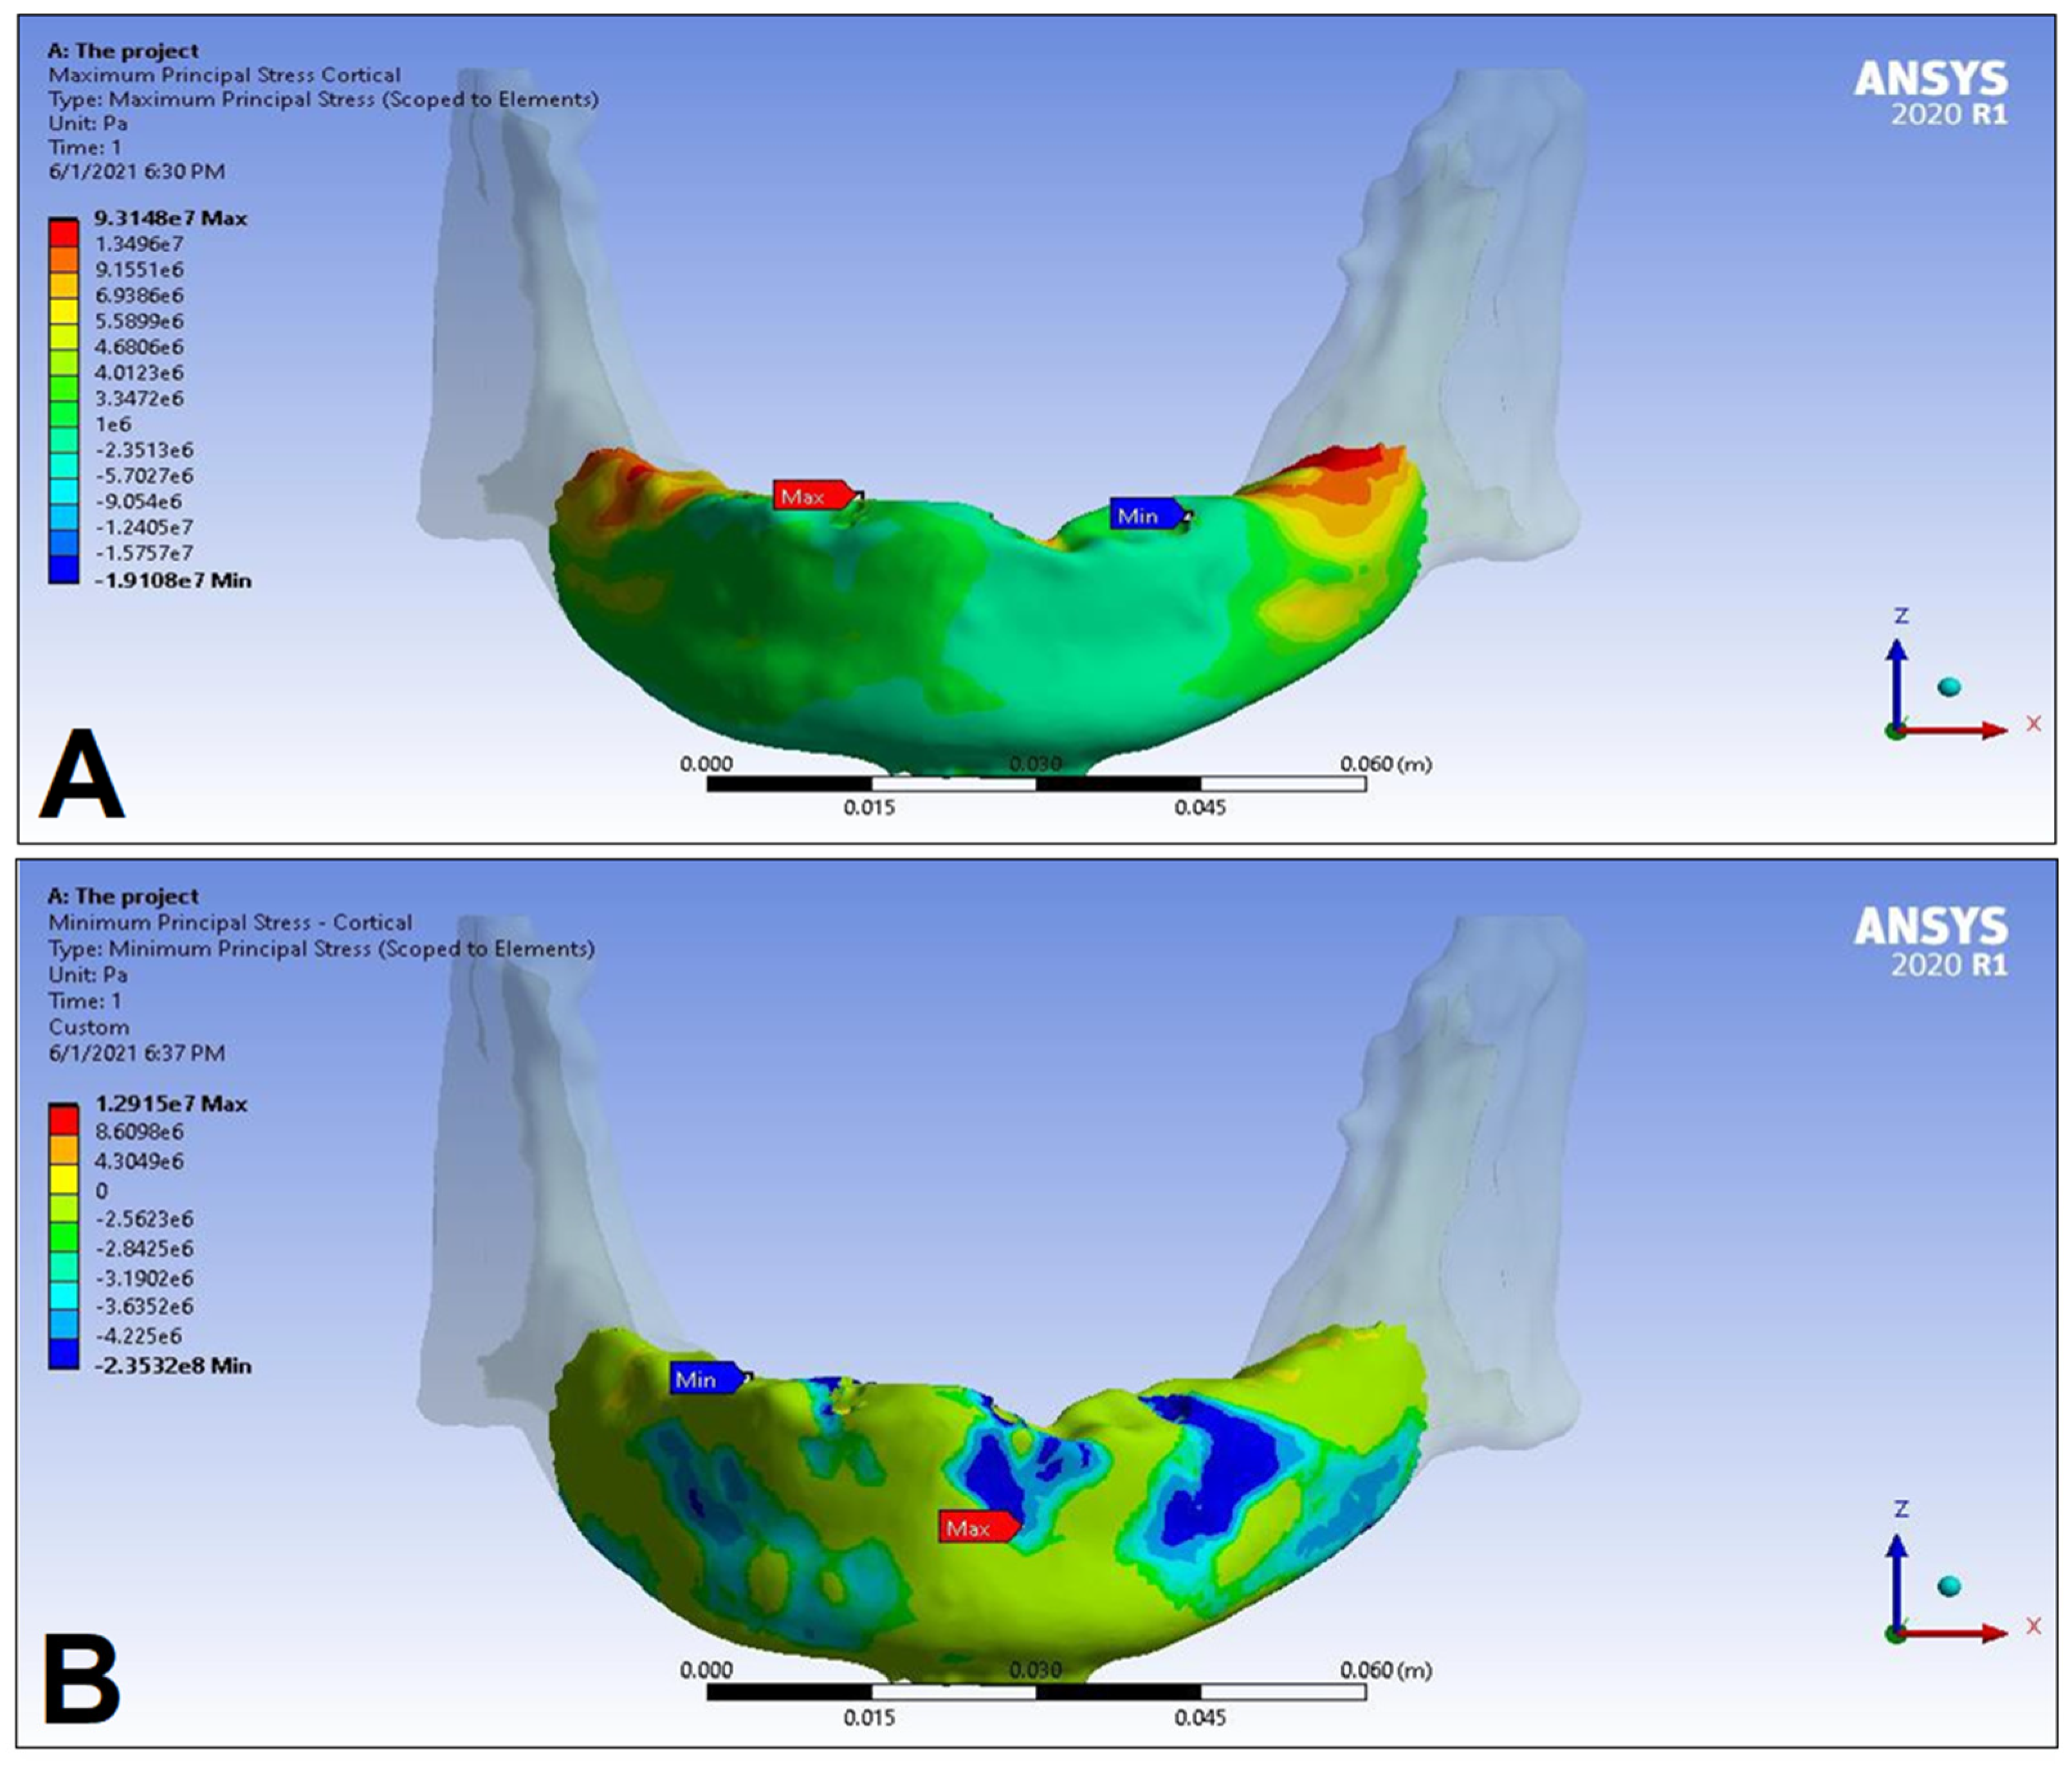

3. Results

| Cortical bone | Pmax [MPa] | 76.39 | 88.51 | 89.57 | 102.98 | 85.63 | 95.48 | 81.02 | 93.15 |

| Pmin [MPa] | −115.30 | −222.76 | −136.4 | −265.35 | −172.30 | −252.61 | −125.20 | −235.32 | |